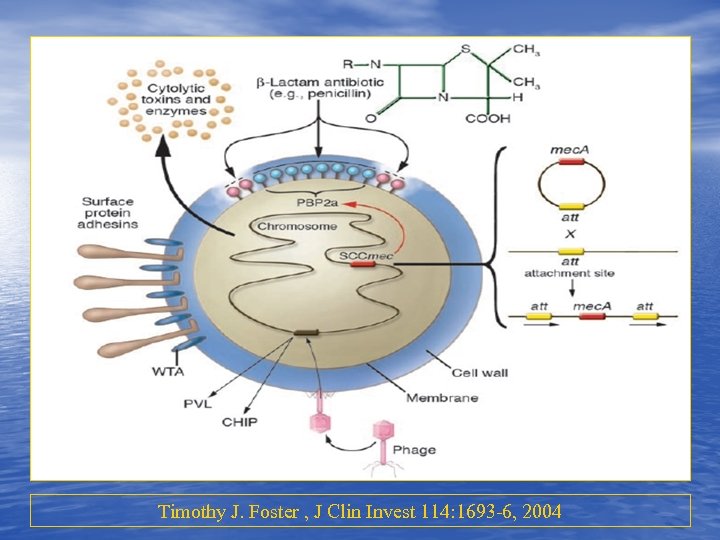

Timothy J. Foster , J Clin Invest 114: 1693 -6, 2004

Timothy J. Foster , J Clin Invest 114: 1693 -6, 2004